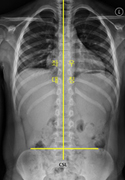

· 측만증치료

척추가 바르지 못한 아이들(소아)과 성장기 청소년에게 변형된 자세와 움직임 패턴을 인지하고,정상적인 자세의 회복을 도모하며 잘못된 자세에 의해 발생되는 손상을 방지합니다.

- 치 료 전

-

- 치 료 전

- 치 료 후